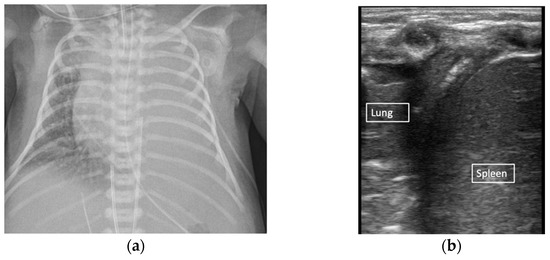

Neonatal LUS is an evaluation and interpretation of normal lung artifacts. LUS identifies the subcutaneous tissue, muscle, ribs, and pleural line (visceral and parietal pleura interface) (Figure 1). Normal LUS artifacts include reverberation artifacts (A-lines), comet tail artifacts (B-lines), and acoustic shadowing artifacts (rib shadowing). Specific LUS terminology is used to describe the artifacts commonly seen in neonatal LUS (Figure 2).

Figure 1. Lung ultrasound artifacts. B-model normal lung (a) B-model respiratory distress syndrome (b).